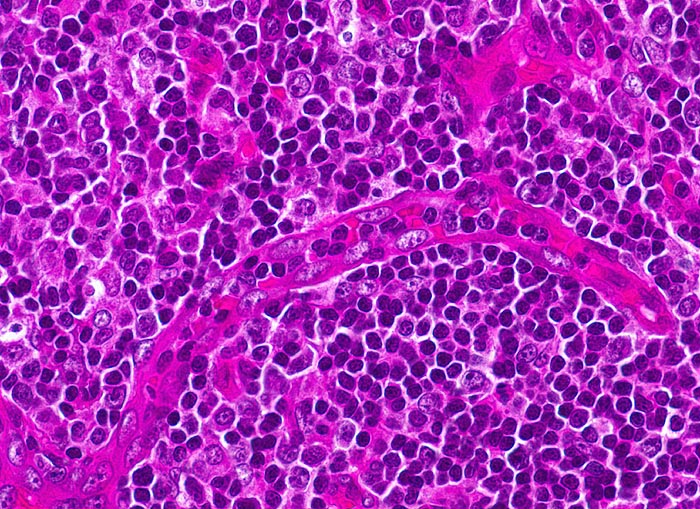

In vielen Fällen entspricht das zytologische Bild bei Mononukleose einer gewöhnlichen reaktiven follikulären Hyperplasie. Seltener findet sich das typische bunte Bild mit vielen plasmozytoiden Zellen und grossen, manchmal doppelkernigen Blasten vom Typ der Zentro-, Immuno- oder Plasmoblasten. Auch Plasmazellen und Granulozyten kommen vor. Stark aktivierte lymphoide Zellen können zur Verwechslung mit einem malignen Lymphom führen.

Die zytologischen Bilder stammen von einem Lymphknoten, die Histologie von einer Tonsille. Die morphologischen Veränderungen bei Mononukleose in diesen beiden Organen sind vergleichbar.